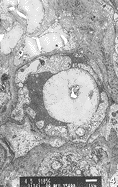

20例NIDDM病人胃粘膜微血管均有不同程度显著改变。 微血管内皮细胞均有不同程度的肿胀 , 内皮细胞的厚度是对照组内皮细胞的几倍乃至十几倍。 有1例血管内皮细胞呈气球样肿 胀, 并突向管腔, 堵塞血管腔约4/5(图1)。 胞浆形成大量指状突起伸入管腔, 有的突起 呈犬齿状, 有的互相连成网状, 与红细胞发生缠绕现象(图2)。 吞饮小泡明显增多, 大 部分吞饮小泡集中于细胞的腔面及基底面两侧。 胞浆内可见肿胀的线粒体, 有的呈空泡状 。 少见高尔基氏器及粗面内织网。 细胞连接缝隙增宽窗孔增大, 有的由于内皮细胞的肿 胀而使窗孔减少甚至消失, 有2例内皮细胞内膜部分有破损, 血小板和红细胞聚集在受损 面上。 微血管基底膜均有不同程度增厚。 有的同一病例显示部分微血管基底显著增厚, 而部分微血管基底膜增厚较轻, 提示为一种微血管的节段性基底膜增厚。 有的微血管基底 膜在内皮细胞外和周细胞周围呈层状增厚(图3)。 周细胞在胃粘膜微血管中出现较少。 周 细胞以一种不完全的包绕微血管的形式存在, 其内侧基底膜和外侧基底膜显示了同等的厚 度。 我们根据电镜下胃粘膜微血管受损程度将其分为轻、 中、 重三级。 轻度: 微血管 内皮细胞轻度肿胀, 管腔无明显狭窄, 无胞膜损害, 基底膜轻度增厚。 中度: 微血管 内皮细胞肿胀, 管腔稍变窄, 不闭锁。 基底膜增厚较明显(图4)。 重度: 微血管内皮细 胞高度肿胀, 内膜受损, 管腔狭窄, 甚至闭锁。 基底膜明显增厚。 本组20例NIDDM胃粘 膜微血管的电镜观察结果: 轻度受损2例; 中度受损16例; 重度受损2例。

图2 NIDDM 患者胃粘膜微血管内皮细胞缠绕细胞×5000